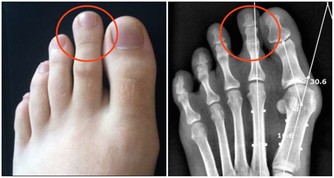

一直呆在空調房裡,傷關節、易惹空調病

- 膝蓋、頸椎等關節部位特別容易受冷風侵襲,引起頸椎病、肩周炎、風濕、類風濕等。

4、休息時,關節暴露部位可適當加蓋毛巾被。每隔1小時活動身體,如搓手、按脖子、轉動關節等。